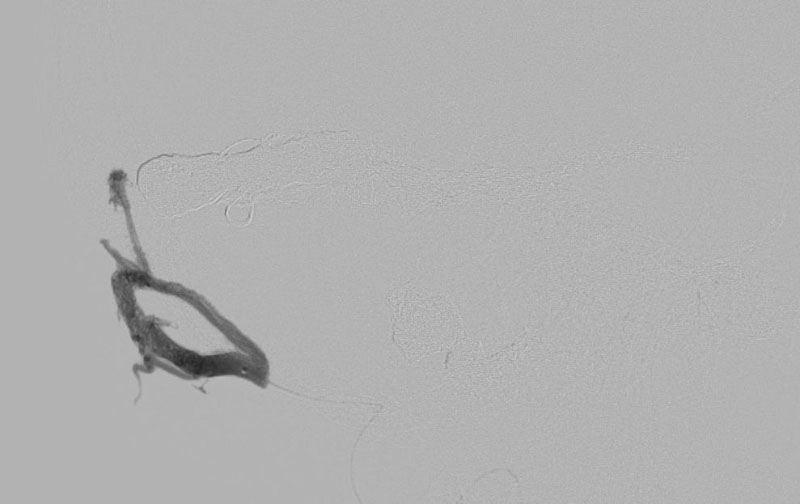

症例 '22年1月

No.

1179

'22年1月12日

左硬膜動静脈瘻

80代

院内外来

手術写真

治療

前

中

後

手術日